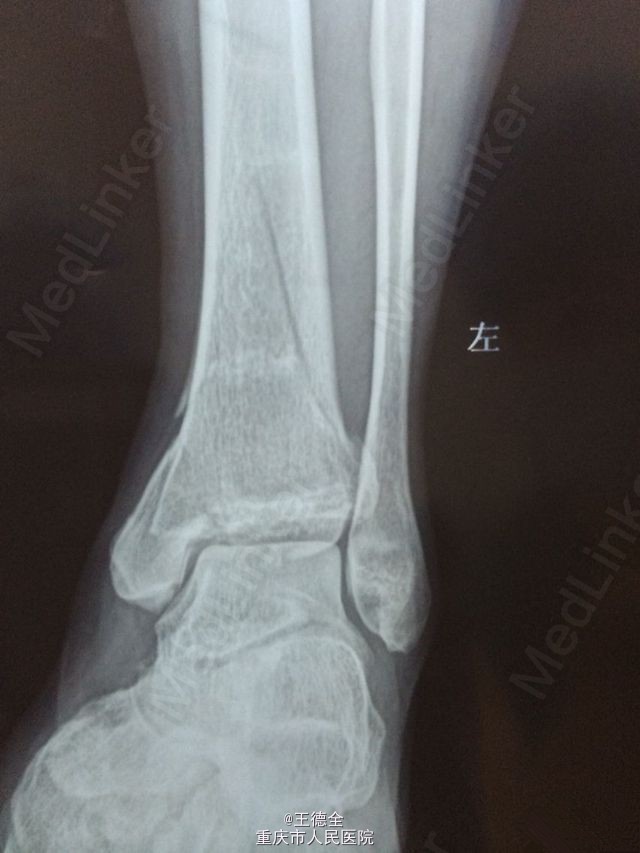

左脚pilon骨折一例

患者老年男性,高出摔落伤,查体:左踝部中度肿胀,畸形,压痛,活动受限,足背动脉波动好,足趾运动及末梢血运、感觉正常。